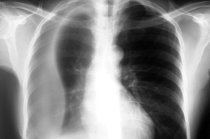

Geralmente, as auscultas cardíaca e pulmonar já fornecem indícios do derrame4 pleural, mostrando uma área de silêncio, no tórax12, mas para confirmar o diagnóstico13 é necessário uma radiografia do tórax12. Coleções líquidas muito pequenas só podem ser diagnosticadas por meio da tomografia computadorizada14 ou da ultrassonografia15. Uma vez constatada a presença de líquido, o mesmo pode ser retirado por toracocentese16 (punção do líquido com uma agulha introduzida através do tórax12, entre as costelas17) e analisado em laboratório quanto a seus aspectos físicos, presença de células18 e composição química. Se necessário pode-se ainda realizar um toracoscopia, com introdução de um endoscópio (aparelho contendo em sua extremidade uma câmera de filmagem) dentro da cavidade pleural19 para visualização da pleura1 e dos pulmões2 e eventual realização de uma biópsia20.